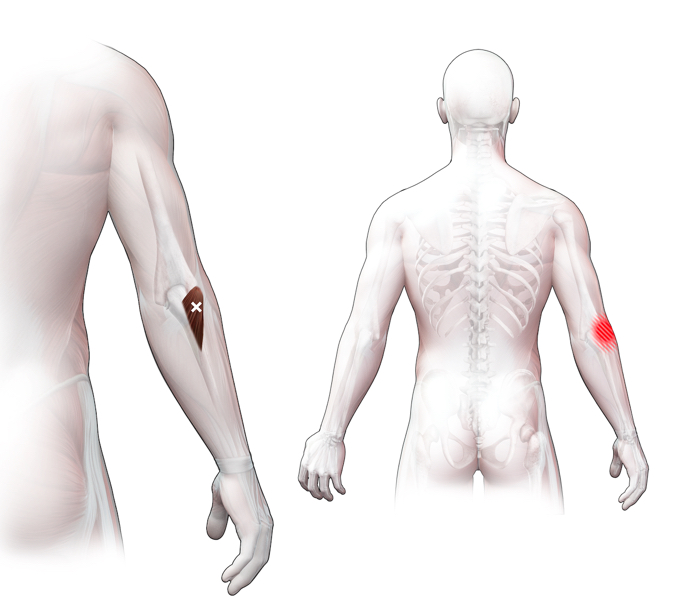

Spieren (Nederlands)

Spieren (nederlands)

Spieren (Latijn)

Spieren (latijn)